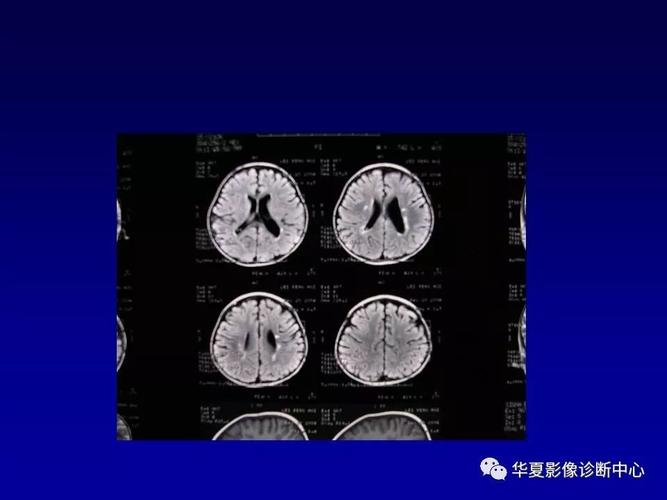

脑白质软化,脑白质脱髓鞘

图文详解脱髓鞘脑病影像诊断

脑白质病变的影像学鉴别诊断

脑白质病变